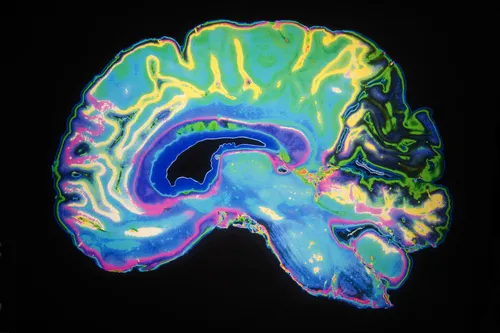

brain-scan-dilantinThe epilepsy drug Dilantin (Phenytoin) may be linked to a risk of cerebellar atrophy, a condition where the cerebellum shrinks to a much smaller size than normal, according to a medical study.

The researchers conducted a study of epilepsy patients who used phenytoin over a period of two months.  Through the use of MRI scans, the researchers looked at cerebellar volumes and determined that a portion of patients showed signs of cerebellar atrophy.